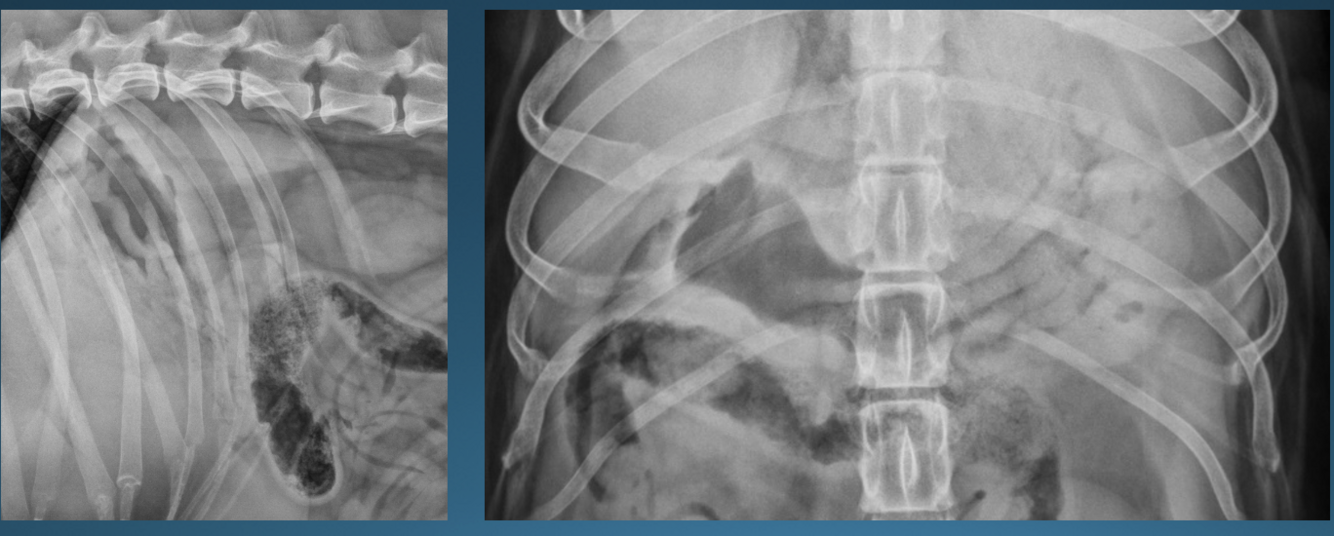

What is shown in these images?

A

left: normal canine stomach

right: normal feline stomach